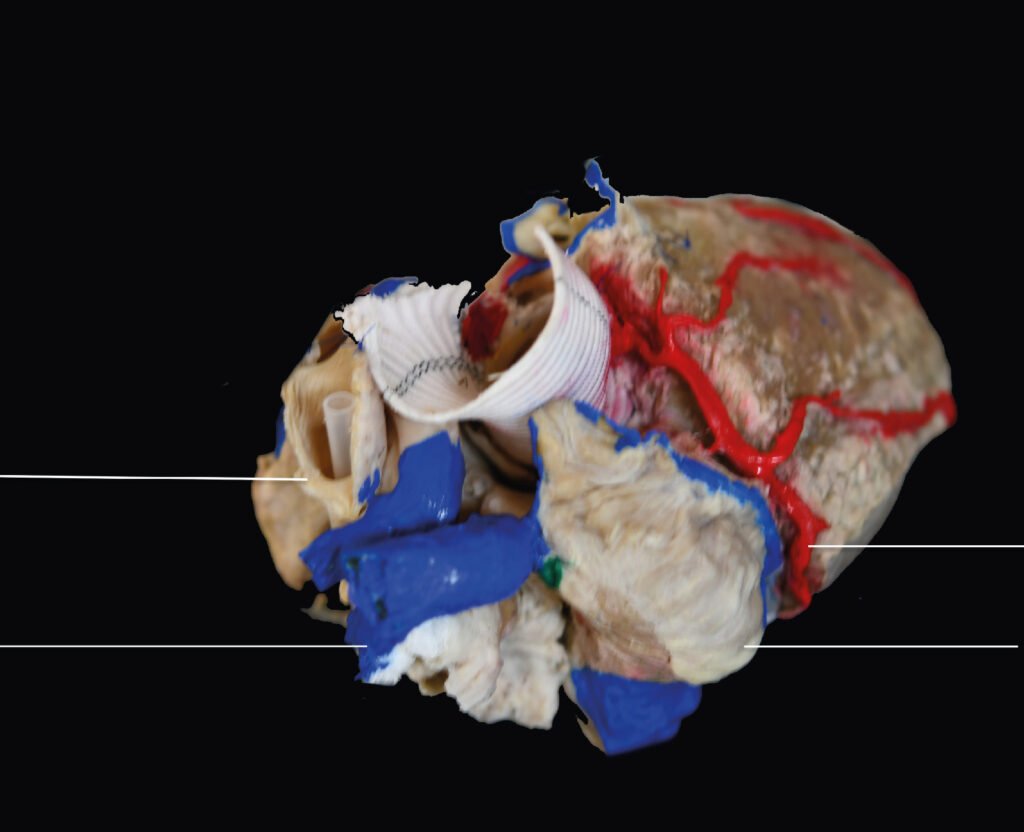

Museo.

Encontrarás los preparados de nuestro laboratorio en el museo de Anatomía J. J. Naón, Facultad de Medicina, Universidad de Buenos Aires, con su descripción.

Encontrarás los preparados de nuestro laboratorio en el museo de Anatomía J. J. Naón, Facultad de Medicina, Universidad de Buenos Aires, con su descripción.